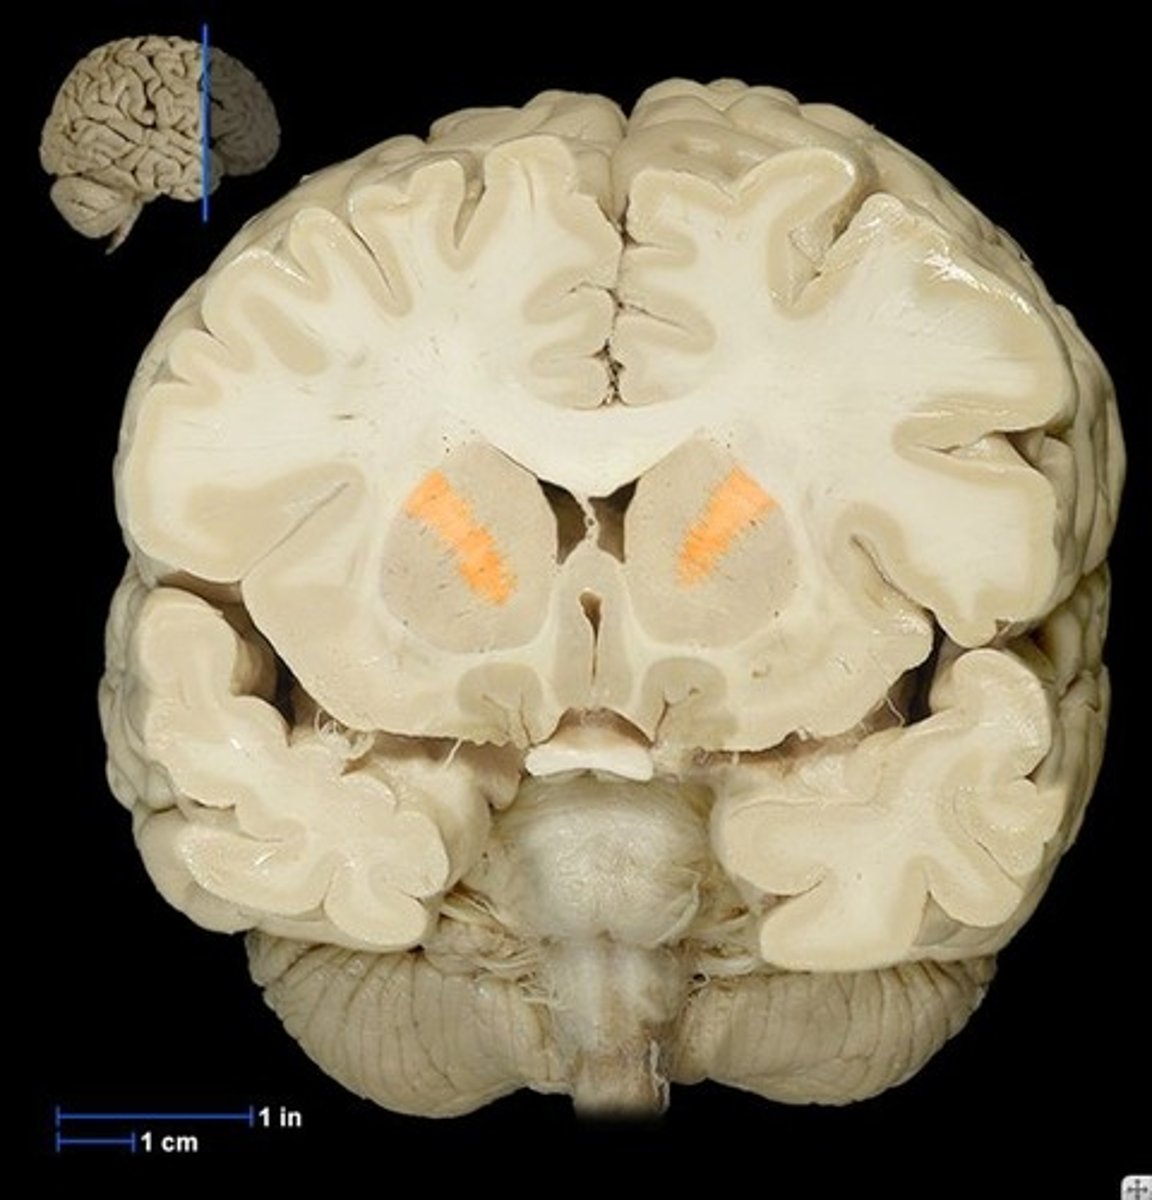

Coronal View